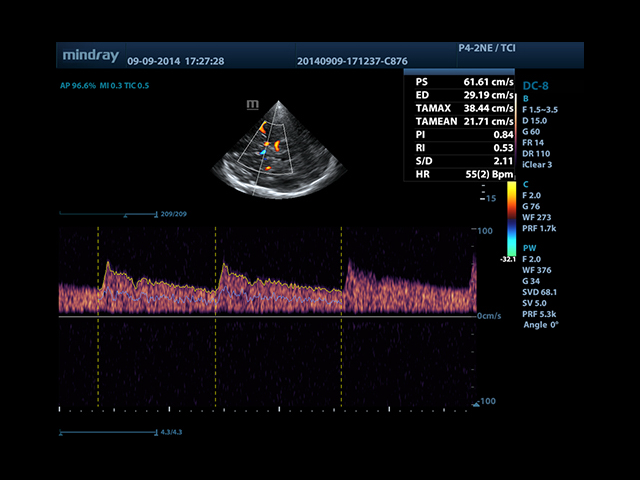

• Автоматическая трассировка допплеровского спектра с расчетом параметров и индексов

• Smart Doppler™ - автоматическая подстройка расположения рамки цветового допплера и контрольного объема импульсно-волнового допплера